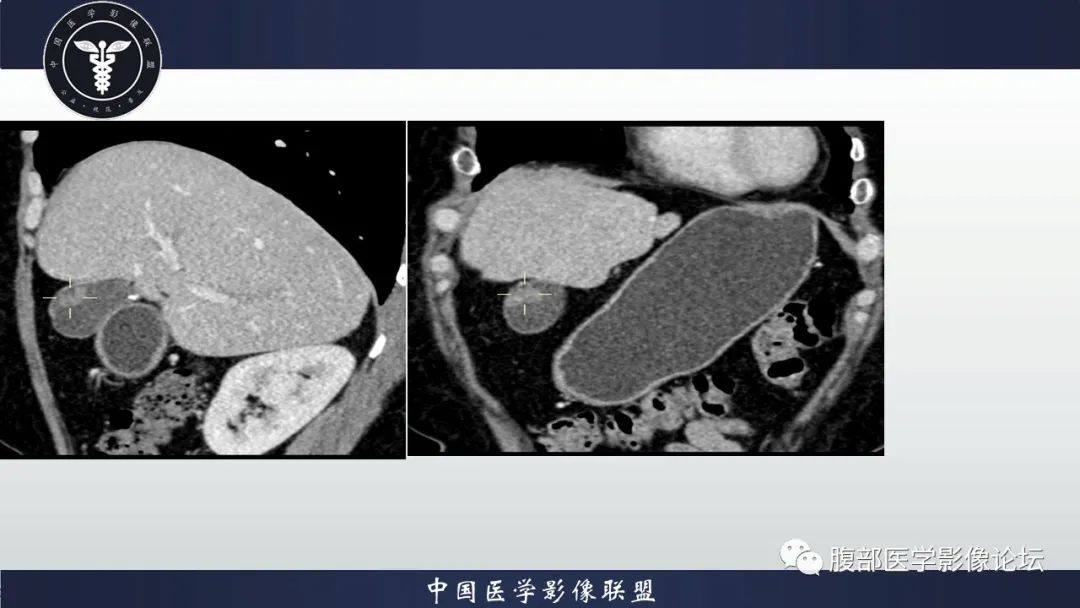

【病例】胆囊管状腺瘤1例CT及MR影像表现-3

【病例】胆囊管状腺瘤1例CT及MR影像表现-4